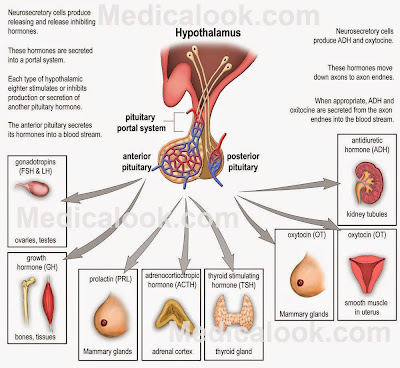

So what controls much of this neuroendocrine system? Your brain of course. Well, a small part of your brain that's pretty old in terms of evolution (even primitive hagfish have a pituitary). The hypothalamus senses many of the inputs that tell your brain just how well your body is maintaining homeostasis. If something goes astray, or if there is a change in your environment that forces a change in your body chemistry, the hypothalamus will then spring into action (O.K., it’s always working, it will just work harder).

The hypothalamushas a neuroendocrine relationship with the pituitary gland (better named the hypophysis, where hypo = under and physis = growth – it is a growth under the brain). The hypophysis comes in two parts. Both parts release hormones, but where those hormones come from and the sources of the tissues of the two pituitary parts are very different.

The anterior pituitary isn’t part of the brain at all. The tissue for the adenohypophysis(anterior pituitary, adeno = secreting) comes from the roof of the embryonic mouth. It is epithelial in origin and has cells that produce hormones in response to signals from the hypothalamus (also hormones). Here’s how it happens.

Well, it gets worse. There are six releasing hormones from the hypothalamus that stimulate production and release of seven hormones from the adenohypophysis that then act on at least 20 endocrine glands and neuroendocrine cell types. Hypothalamus to adenohypohysis to endocrine gland – it’s called an axis, and there are several of them.

On the other hand, the posterior pituitary (neurohypohysis) is derived from brain tissue. Instead of the neurons of the hypothalamus producing releasing hormones that then act on the neurohypophysis, the hypothalamic neurons project right into the posterior pituitary where they deposit their hormones (oxytocin and antidiuretic hormone). The neurohypophysis doesn’t make any hormones itself, it just stores what the hypothalamic neurons produce and then releases them to the circulatory system.